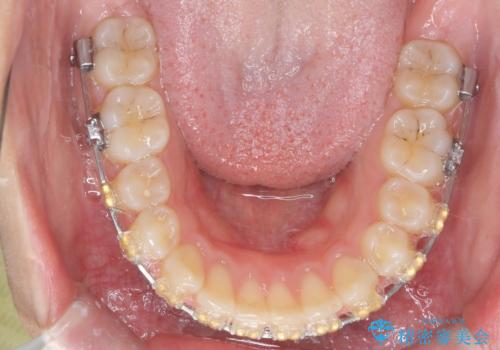

深い噛み合わせ、すきっ歯の改善 ワイヤーを用いたマルチブラケット矯正

- 噛み合わせが深く、前歯が突き出て隙間が出てきたことの改善を希望され矯正治療の相談で当院に初診来院されました。

ワイヤーを用いたマルチブラケット矯正を行うことで深い噛み合わせを改善し、前歯の隙間もなくし審美的な歯列へと治療をおこなっていきます。

深い噛み合わせの改善は前歯の圧下が必要なため、治療期間が長期化することが多いです。